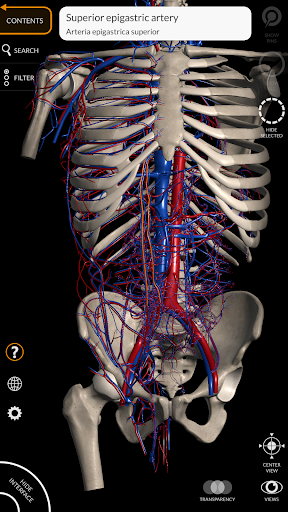

"Anatomy 3D Atlas" memungkinkan Anda mempelajari anatomi manusia dengan cara yang mudah dan interaktif.

Melalui antarmuka yang sederhana dan intuitif, Anda dapat mengamati setiap struktur anatomi dari sudut mana pun.

Model 3D anatomi sangat terperinci dan memiliki tekstur hingga resolusi 4k.

• Sistem kardiovaskular • Sistem

saraf • Sistem pernapasan • Sistem pencernaan • Sistem urogenital (pria dan wanita) • Sistem endokrin • Sistem limfatik • Sistem mata dan telinga FITUR • Antarmuka yang sederhana dan intuitif • Putar dan perbesar setiap model dalam ruang 3D • Opsi untuk menyembunyikan atau mengisolasi satu atau beberapa model yang dipilih • Filter untuk menyembunyikan atau menampilkan setiap sistem • Fungsi pencarian untuk menemukan setiap bagian anatomi dengan mudah • Fungsi penanda untuk menyimpan tampilan khusus • Rotasi cerdas yang menggerakkan pusat rotasi secara otomatis • Fungsi transparansi • Visualisasi otot melalui tingkat lapisan dari yang superfisial hingga yang terdalam • Dengan memilih model atau pin, istilah anatomi terkait akan muncul • Deskripsi otot: asal, • Tampilkan/ Sembunyikan antarmuka UI (sangat berguna dengan layar kecil) MULTIBAHASA • Istilah anatomi dan antarmuka pengguna tersedia dalam 11 bahasa: Latin, Inggris, Prancis, Jerman, Italia, Portugis, Turki, Rusia, Spanyol, Mandarin, Jepang, dan Korea • Istilah anatomi dapat ditampilkan dalam dua bahasa secara bersamaan PERSYARATAN SISTEM • Android 8.0 atau yang lebih baru, perangkat dengan RAM minimal 3GB Reversi

• Sistem kardiovaskular